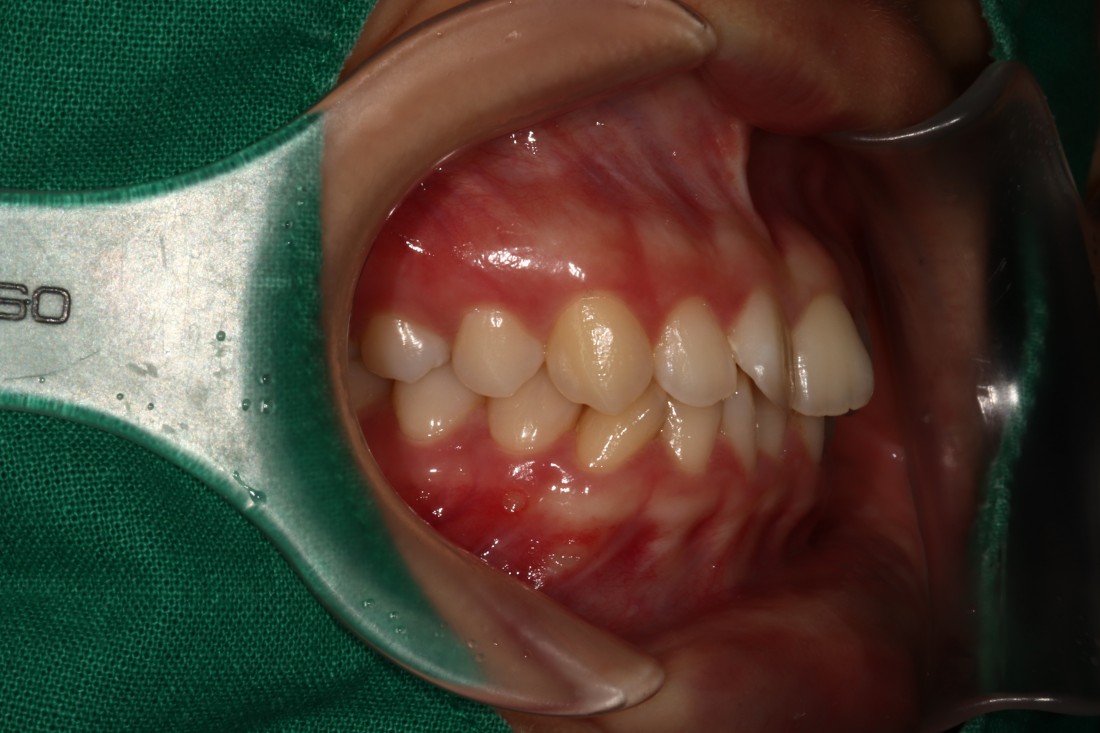

광주 교정치과는

200케이스 넘는 교정사례를

상세하게 공유해드리고 있기 때문에

실력을 믿고 맡기셔도 좋습니다.

더 다양한 교정 전/후 사례는

위의 사진을 클릭하시면

확인하실 수 있습니다.